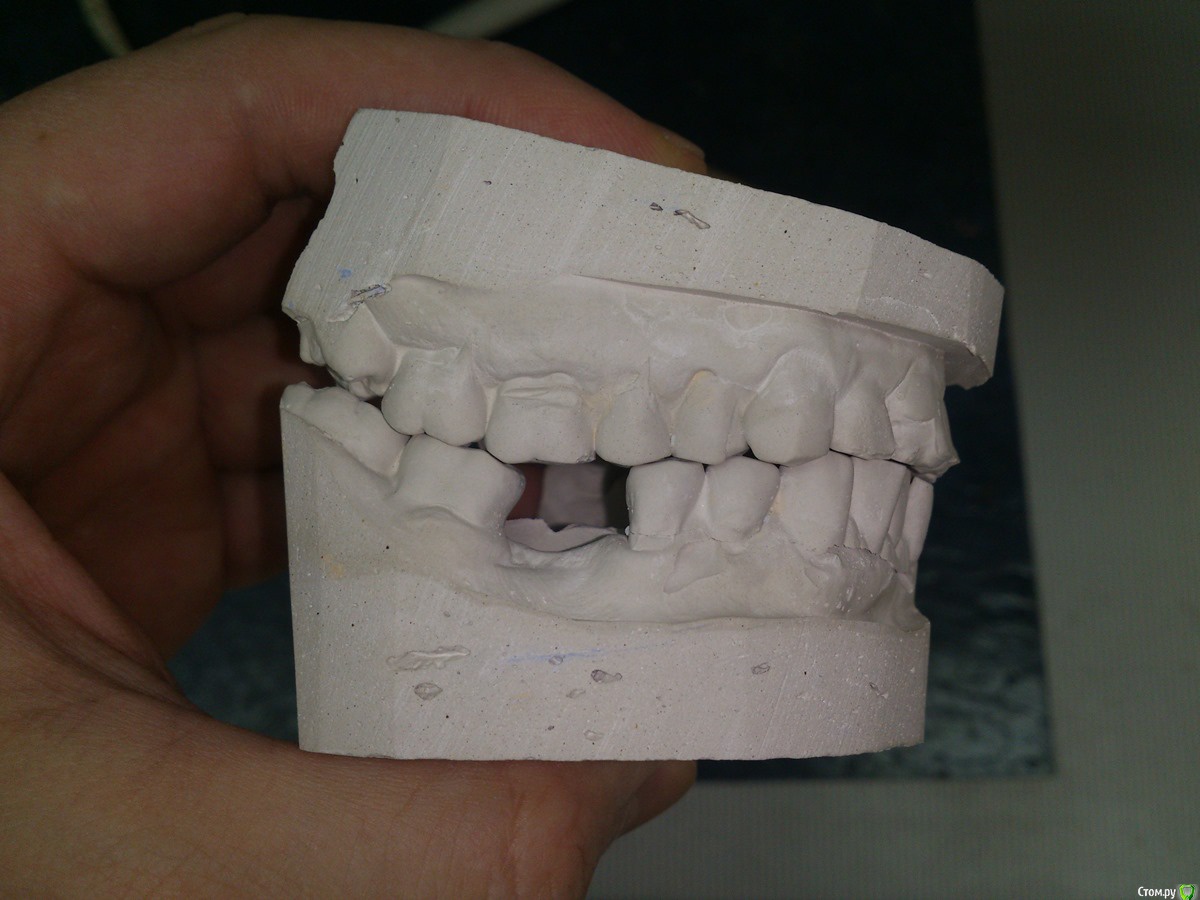

Sampson Опубликовано 7 февраля, 2016 Поделиться Опубликовано 7 февраля, 2016 Если без тотала.1)Снимок. Уз чистка2)Стераемость 13.23/33.43.Востанавливаем клыковую направляющую.3)Эндолечение и попутное поднятие прикуса на накусочных площадках. 4)Времянки Ссылка на комментарий

Ronin Опубликовано 7 февраля, 2016 Поделиться Опубликовано 7 февраля, 2016 Решение оптимальное, как сказал коллега выше, восстановить фронт и клыковое ведение, но как ограничиться этим, ведь бока тоже нужно делать.. там же эндо, как я понял и так делается, одного моляра нет?! реставрации композиционные что ли? Надо учитывать "стискивание" , разломает потом эти зубы и все, плюс расхождение зубов тоже есть, перегрузка, не забудем и про пародонтальный комплекс, высоту поднять, если нужно, предварительно определив, хотя высота, как мне кажется в порядке, но могу ошибаться, на завершающем этапе обязательно каппу, ношение максимальное время! Здесь важно хуже не сделать, если нет уверенности в стабильном результате, ибо не навреди... Если уверенны, то только в путь))) Ссылка на комментарий

SanderS Опубликовано 8 февраля, 2016 Автор Поделиться Опубликовано 8 февраля, 2016 те что после перелечивания естественно будут покрываться коронками, нижний моляр имплантат, если пришеечные дефекты реставрировать композитом при условии восстановления клыковой направляющей + каппа, не повыпадают ли они? Высота у него вроде не снижена, за счет компенсации. Ссылка на комментарий

Ronin Опубликовано 8 февраля, 2016 Поделиться Опубликовано 8 февраля, 2016 Обратите внимание на 47, если имплантат планируете, то решите пародонтологически страгию, чтоб потом благополучно не расстаться с импл и зубом, 35,36,37 - аналогичная ситуация, пародонтология.Если мероприятия все же будут минимальны, то всегда каппа, максимальное ношение уже сейчас, если не будет реконструкции жевательных плоскостей Ссылка на комментарий